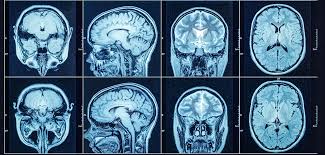

Accurate diagnosis is the first step toward effective treatment. We understand the importance of quick and precise diagnostic services, which is why we offer CT Scan in Pakur at our facility.

Our advanced CT scan unit helps in the early detection of various conditions such as internal injuries, tumors, neurological issues, and more. Patients no longer need to travel far for such services, as they can access these diagnostics locally with assured quality and accuracy.